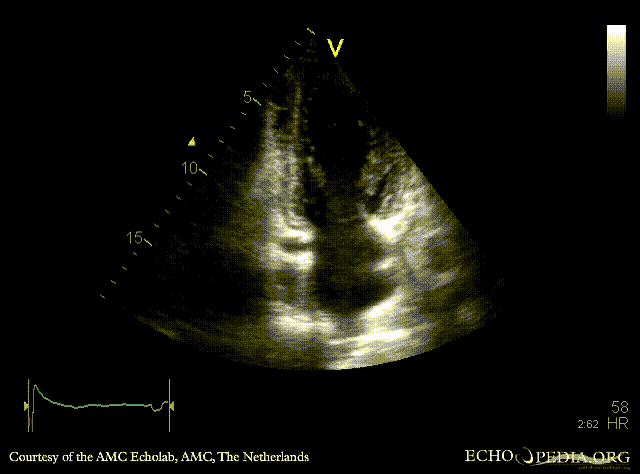

A4CH: normal systolic function of left ventricle A2CH

A3CH Pulsed-wave Doppler signal of mitral inflow: E>A